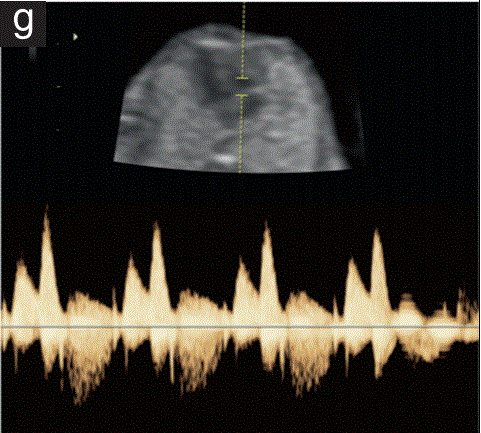

三尖瓣血流

通过识别胸腔横断面四腔切面,使心脏心尖出现在12点或6点位置来评估通过三尖瓣的流量。在三尖瓣前瓣上放置一个2-4mm的脉冲取样框,取得波形(图1g)。

三尖瓣反流被定义为血流>为60 cm/s,>为50%的心周期。这种二分变量在整倍体胎儿中很少异常,并与高阳性和负似然比相关。

胎儿mt是什么检查什么疼吗【文献学习/规范指南】ISUOG实践指南(2023更新): 11-14周胎儿超声检查(全文)_https://www.jmylbn.com_新闻资讯_第32张

图1 11+0至14+0周胎儿超声检查可获得的测量值。

(g)胎儿胸部心脏四腔水平横断切面,脉冲多普勒检查显示三尖瓣速度波形正常,无三尖瓣反流。心脏轴见图2j。